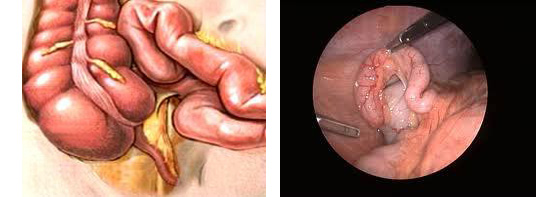

Το οξύ άλγος χωρίς την τυπική εικόνα της σκωληκοειδίτιδας, είναι η κύρια ένδειξη για λαπαροσκοπική σκωληκoειδεκτομή. Με τον τρόπο αυτό άλλες καταστάσεις όπως μεσεντέρια αδενίτιδα, έκτοπη κύηση, σαλπιγγίτιδα, συστροφή κύστεως ωοθήκης, ινομυώματα κ.α. μπορούν εύκολα να διαγνωστούν και να ακολουθήσει η σωστή αντιμετώπιση.

Οι λέξεις λαπαροσκοπική σκωληκοειδεκτομή περιγράφουν την τεχνική που χρησιμοποιεί ο χειρουργός για να αποκτήσει πρόσβαση στην κοιλία του ασθενούς και να εκτελέσει την επέμβαση για την αφαίρεση της σκωληκοειδούς αποφύσεως.

Χρησιμοποιώντας ένα σκληρό πλαστικό καθετήρα (trocar), ο χειρουργός εισέρχεται στην κοιλιά δημιουργώντας πνευμοπεριτόναιο. Έπειτα ένα λαπαροσκόπιο, (μικροσκοπικό τηλεσκόπιο συνδεδεμένο με μία βιντεοκάμερα) εισάγεται μέσω του trocar , δίνοντας στο χειρουργό μία μεγεθυμένη εικόνα των εσωτερικών οργάνων του ασθενούς σε μια οθόνη τηλεόρασης. Μέσω άλλων trocars ο χειρουργός χειρουργεί και αφαιρεί την φλεγμονώδη σκωληκοειδή απόφυση. Η όλη διαδικασία μπορεί να ολοκληρωθεί μέσα από τα trocars ή με επιμήκυνση σε μία από τις μικρές τομές για την είσοδο των trocars.